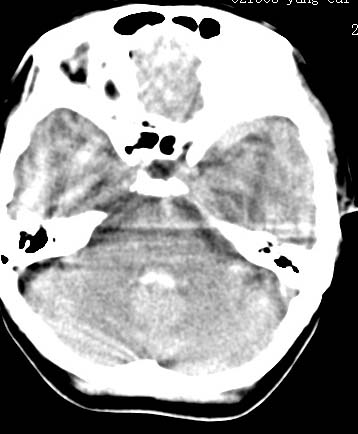

标题: CT9945:男性 病人 请大家看看出血的部位究竟在哪里? [打印本页]

标题: CT9945:男性 病人 请大家看看出血的部位究竟在哪里?

男性 病人 请大家看看出血的部位究竟在哪里?

是不是脑室系统出血啊! 伴轻度脑积水! 请老师指教!!

脑室系统出血,并脑积水.

脑室系统出血,第三脑室,侧脑室都有

最重要的是要讲明以脑室内积血为主,脑积水